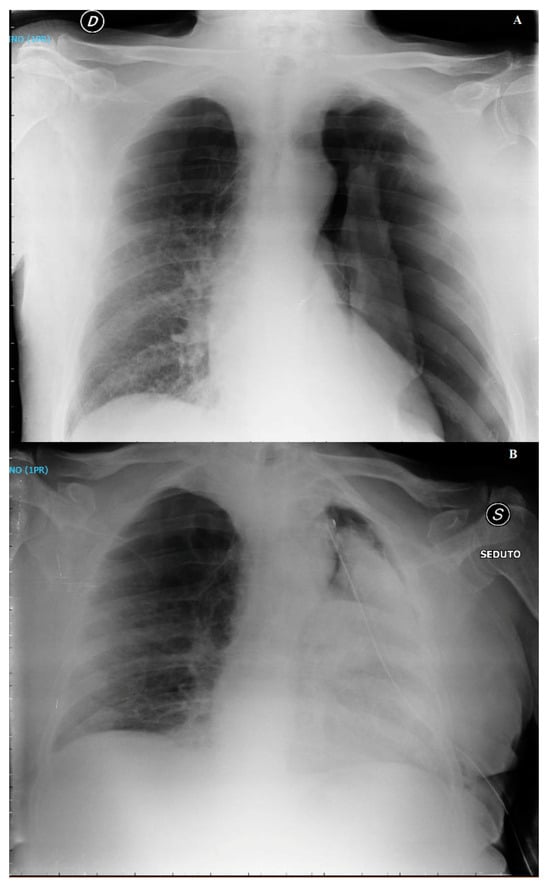

3.2. Case 2